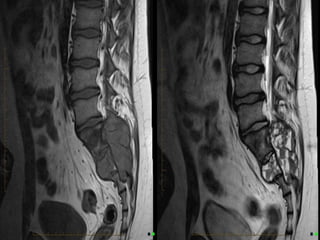

Aneurysmal  Bone  Cyst   •  Benign  expansile  tumor-­‐like  bone  lesion,  contain   numerous  blood  filled  channels   •  Children  and  adolescents  (<20  y.o)   •  X-­‐Ray  :  sharply  defined,  expansile  osteoly:c  lesions,   with  thin  sclero:c  margins   •  CT:  fluid  fluid  levels   •  MRI:  low  signal  of  T1  and  T2,   •  Treatment  :Opera:ve  (Bone  curretage  and  Grafing)